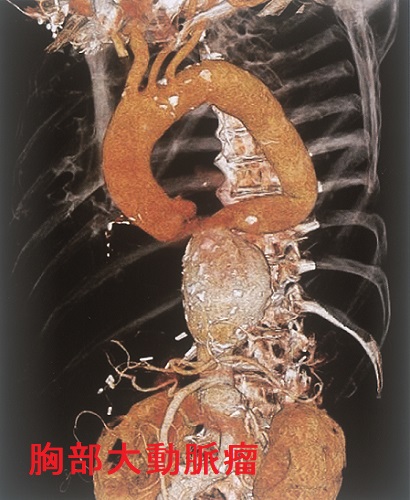

甲状腺機能低下症/潜在性甲状腺機能低下症/橋本病で動脈硬化が進行、急性大動脈解離とDIC・心タンポナーデ、腹部大動脈瘤、甲状腺動脈瘤破裂おこる。急性大動脈解離は血中Dダイマー上昇。A型上行大動脈解離が大動脈基部に及ぶと心臓栄養する冠状動脈入口部を圧迫、急性心筋梗塞と同じ心電図所見に。B型解離(DeBakey III)で主要分枝を含まない領域に限局は降圧治療のみ。甲状腺動脈瘤は血栓塞栓症なく、高率に破裂し死亡率20%のため無症候性でもコイル塞栓術、外科的切除。動脈硬化進行してできる腹部大動脈瘤は破裂すると突然死。通常、無症状で破裂始まると腹痛・腰痛。

動脈硬化が原因でおこる急性大動脈解離、腹部大動脈瘤、甲状腺動脈瘤を以下に解説します。

急性大動脈解離とは、大動脈壁の脆弱さ、動脈硬化、高血圧などが原因で、血管内膜に亀裂が入り、中膜が裂け、内腔側が内膜フラップ(intimal flap)になって、その下に偽腔が生じる病態です。

腹部大動脈瘤(AAA)からの動脈性出血では出血性ショックに至ります。鑑別を要する病気のほとんどが痛みのために血圧が上昇しますが、腹部大動脈瘤破裂は、逆に血圧が低下し、急激な貧血の進行を伴うショックバイタルになります(ここで気付けば上等)。

腹部大動脈瘤破裂が始まれば致死率は80-90%になります。